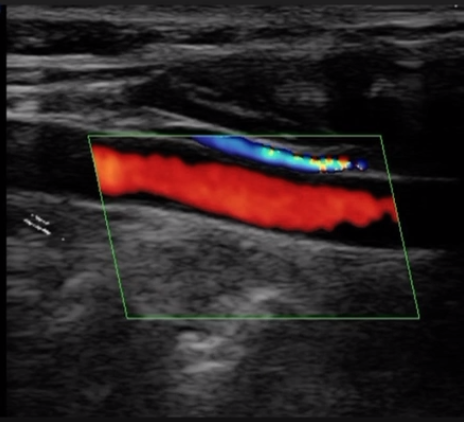

Vascular